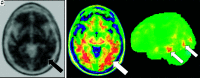

FIG 7.

Axial T1-weighted MR imaging (A) and axial and coronal T1-weighted MR imaging fused with [18F] FDG-PET (B and C) in a left-handed individual with impaired single-word comprehension demonstrate marked asymmetric atrophy of the anterior right temporal lobe (black arrow, A) with corresponding marked hypometabolism (white asterisks, B and C) due to svPPA.

FIG 8.

[18F] FDG-PET (A), axial T1 (B), and PET MR imaging (C) views demonstrate an abnormal FDG distribution pattern with markedly decreased tracer uptake in the temporal lobes, particularly in the left temporal pole. There is corresponding advanced cortical atrophy with a “knife-blade” appearance in the left anterior temporal lobe on the axial T1 sequence.